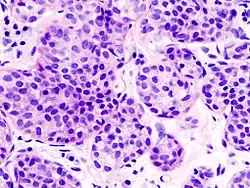

| Pleomorphic | Classical-appearing but with pleomorphic cells. It may include signet-ring cells, or plasmacytoid cells (pictured) which have abundant cytoplasm and eccentric nuclei. | ![]() |